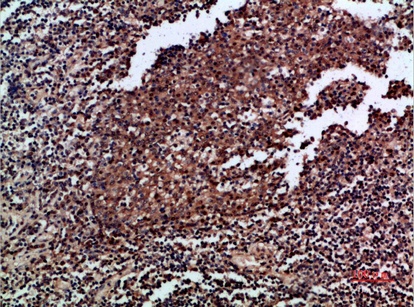

Versatility in applications is another area where ABP58647 shines, catering to the diverse needs of cytokine researchers. It is validated for three core techniques: Immunohistochemistry (IHC), Immunofluorescence (IF), and Enzyme-Linked Immunosorbent Assay (ELISA)—each addressing distinct research goals. For IHC, Abbkine suggests a starting dilution of 1:50–200, making it suitable for visualizing GM-CSF distribution in paraffin-embedded tissues (e.g., human tonsil, as shown in the product’s representative images). For IF (1:50–200 dilution), it enables precise localization of GM-CSF within individual cells, a must for studying cellular responses to inflammation. Notably, its high sensitivity for ELISA (1:10,000–20,000 dilution) allows for quantitative measurement of GM-CSF levels in biological fluids or cell supernatants—an essential capability for experiments quantifying cytokine secretion, such as assessing T cell activation or macrophage response to stimuli. This breadth of applications means researchers can use a single antibody across multiple experiments, ensuring consistency in data.